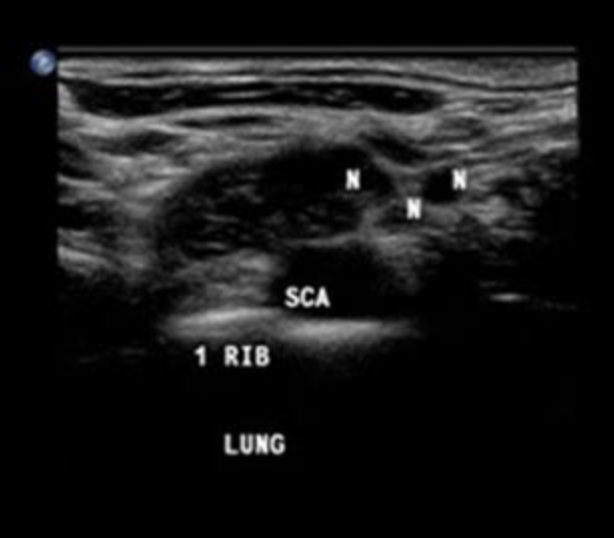

Name the structures seen on this US of the supraclavicular region

N – Nerve

SCA – Subclavian artery

SCM – Sternocleidomastoid